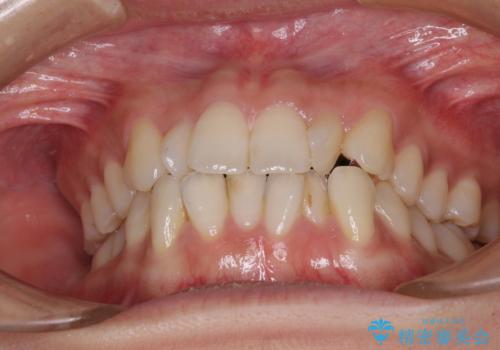

- 上下前歯のねじれを気にして来院された患者様です。

ワイヤー矯正でもマウスピース矯正でも対応可能でしたが、マウスピース矯正の自己管理が面倒であること、上顎前歯の捻転が著しいことから、ワイヤー矯正での治療を希望されました。